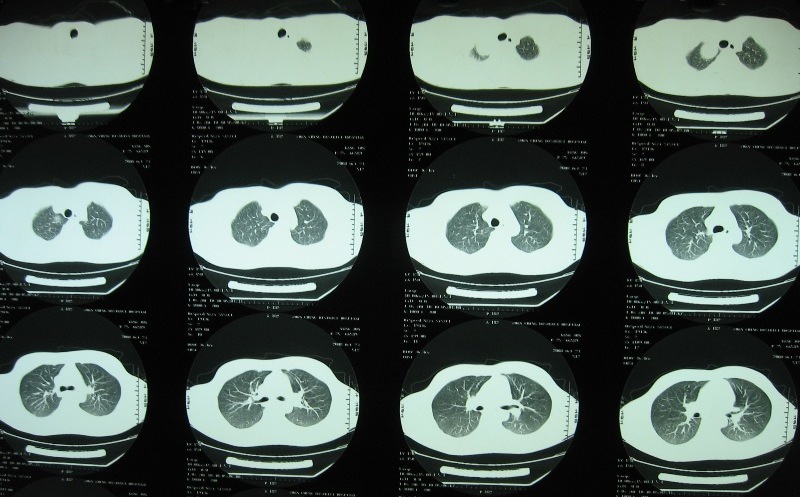

标题: CT16295:男22岁,招工体检发现。自诉右肩不适。 [打印本页]

标题: CT16295:男22岁,招工体检发现。自诉右肩不适。

图像太小了,看不清,考虑气管囊肿可能

根据部位及边缘情况考虑支气管囊肿,可惜图像太小

右上肺尖囊性病变,气管囊肿或肺囊肿都有可能。

图像确实太小,不利于诊断。但纵隔神经源性肿瘤应该没问题。考虑鞘瘤。

支气管囊肿或胸内甲状腺肿,前者可能性大吧